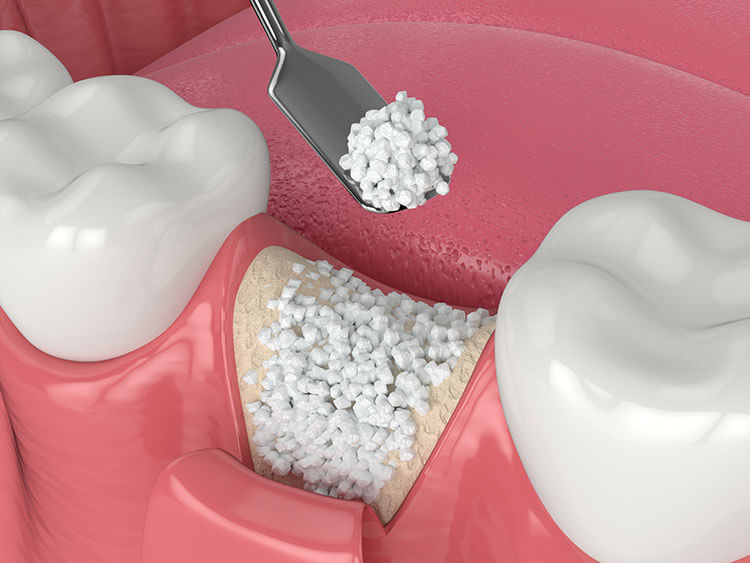

1. آمادهسازی محل جراحی: لثه باز میشود و ناحیه استخوان نمایان میشود.

2. کاشت ایمپلنت: پایه تیتانیومی (فیکسچر) ایمپلنت در استخوان باقیمانده قرار داده میشود.

3. بازسازی استخوان: نواحی فاقد استخوان یا ضعیف، با یکی از مواد پیوندی پر میشود (مثل آلوگرافت، زنوگرافت، یا بیومتریالهای سنتتیک).

4. استفاده از غشا در صورت نیاز: یک غشای مخصوص (غیر قابل جذب یا قابل جذب) روی ناحیه پیوند قرار داده میشود تا از نفوذ سلولهای بافت نرم جلوگیری کرده و فقط سلولهای استخوانساز وارد منطقه شوند.

5. بخیه و بسته شدن ناحیه: در پایان، محل جراحی بخیه میشود و مرحله ترمیم شروع میشود.

فرم ارسال پاسخ

تحلیل استخوان فک داشتم برای ایمپلنت، دکتر محمودی برام تزریق پودر استخوان انجام دادن و باید بگم نتیجه خیلی بهتر از انتظارم بود! استخوان فکم بهخوبی ترمیم شد و فضای مناسبی برای ایمپلنت فراهم شد. کاملاً راحت و بدون درد بود و پزشک تمام مراحل را با دقت و دلسوزی انجام داد. از دکتر محمودی و گروه مشاوره بابت مراقبت و توجهشون خیلی ممنونم و دوستانی که این مشکل رو دارند این مجموعه رو پیشنهاد میکنم.

اگر مثل من نگرانی درباره بازسازی استخوان دارید، باید بگم که این کار اصلاً ترسناک یا دردناک نیست. دکتراز پودر استخوان استفاده کرد و توضیح داد که این فرآیند باعث میشود ایمپلنت بهخوبی در استخوان ثابت بشه. بهبودی خیلی سریع بود و حالا هیچگونه مشکلی ندارم. بهطور کلی از تجربهام بسیار راضی هستم و از کسانی که نیاز به بازسازی استخوان دارند، قطعاً پیشنهاد میکنم این کار رو انجام بدن.